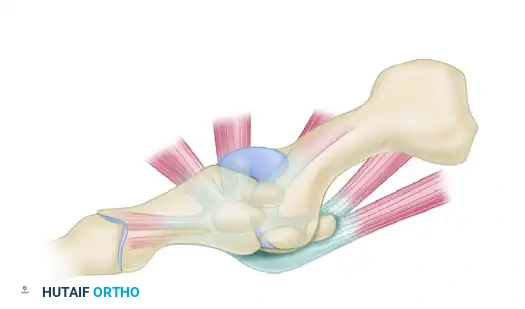

FIGURE 88-78 A: Normal anatomy of the first metatarsophalangeal joint, demonstrating the relationship of the metatarsal head to the proximal phalanx and the underlying sesamoid complex.

The plantar plate is a thick, fibrocartilaginous structure that originates from the metatarsal neck and inserts firmly onto the plantar base of the proximal phalanx. Embedded within the flexor hallucis brevis (FHB) tendons are the medial (tibial) and lateral (fibular) sesamoids, which articulate with the plantar aspect of the first metatarsal head.

Clinical Pearl: The sesamoids function as a fulcrum, increasing the mechanical advantage of the FHB and protecting the flexor hallucis longus (FHL) tendon, which glides between them. The intersesamoid ligament connects the two sesamoids; its integrity dictates the reducibility of the dislocation.

The collateral ligament complex consists of the proper collateral ligaments (connecting the metatarsal head to the proximal phalanx) and the accessory collateral ligaments (connecting the metatarsal head to the plantar plate and sesamoids). Rupture or avulsion of these ligaments, particularly the tibial collateral ligament, is a hallmark of lateral or dorsal dislocations.

In a Type I dislocation, the intersesamoid ligament remains intact. The entire plantar plate and sesamoid complex are avulsed from their metatarsal attachment and displace dorsally over the metatarsal head.

FIGURE 88-78 B: Type I dislocation. The intact intersesamoid ligament traps the metatarsal head, making closed reduction impossible.

Surgical Warning: Type I dislocations are almost universally irreducible by closed means. The metatarsal head becomes tightly incarcerated between the FHB tendons, the intact intersesamoid ligament, and the plantar plate. Applying longitudinal traction without hyperextension will only tighten this "noose" around the metatarsal neck.